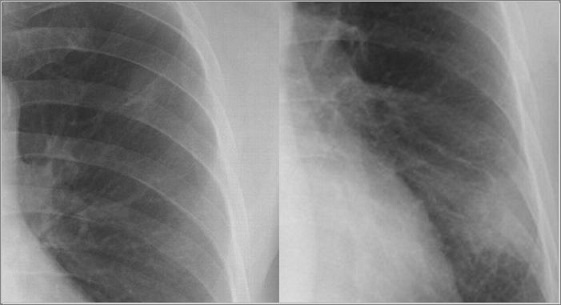

肺結核腫と肺癌のレントゲンは以下のように映り方に差がわかることもある。

左:結核腫 vs 右:肺がん